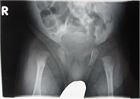

1. 乳児可能性股関節炎を疑う場合には、早急な診断確定が必要である(推奨度1)

1. 診断確定には血液検査と共にMRIが推奨される(推奨度1)

1. 診断確定後は速やかに外科的処置と抗菌薬の全身投与を開始する(推奨度1)